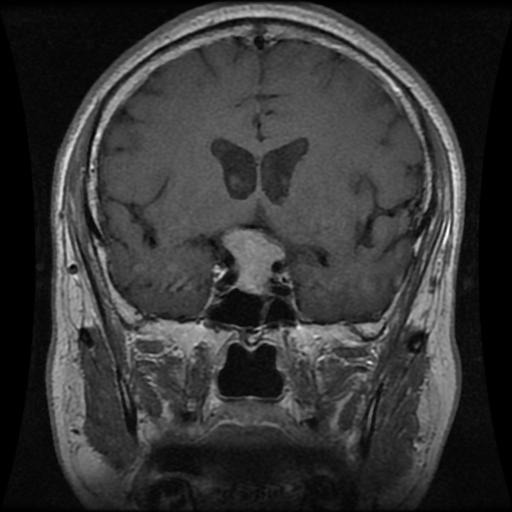

Meningioma

Meningioma

Meningioma

Meningioma